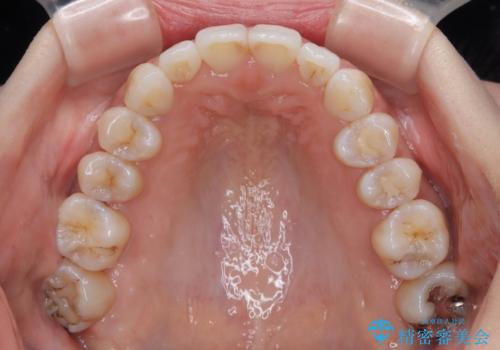

補助装置を用いて奥歯の咬み合わせを事前に改善 インビザラインによる矯正治療

歯列としてはインビザラインでもワイヤー矯正でも対応できるものでしたが、奥歯の咬み合わせを見た時に上顎がやや前方にあり、インビザライン単独では時間のかかってしまう可能性があるため、補助装置を治療当初に使用することで、インビザラインによる治療をスムーズに行えるように計画しました。

インビザラインは得意・不得意の差がはっきりとしているため、補助装置やワイヤー装置などをうまく活用することで、治療期間を短縮するとともに、より理想的な仕上がりを達成することができます。